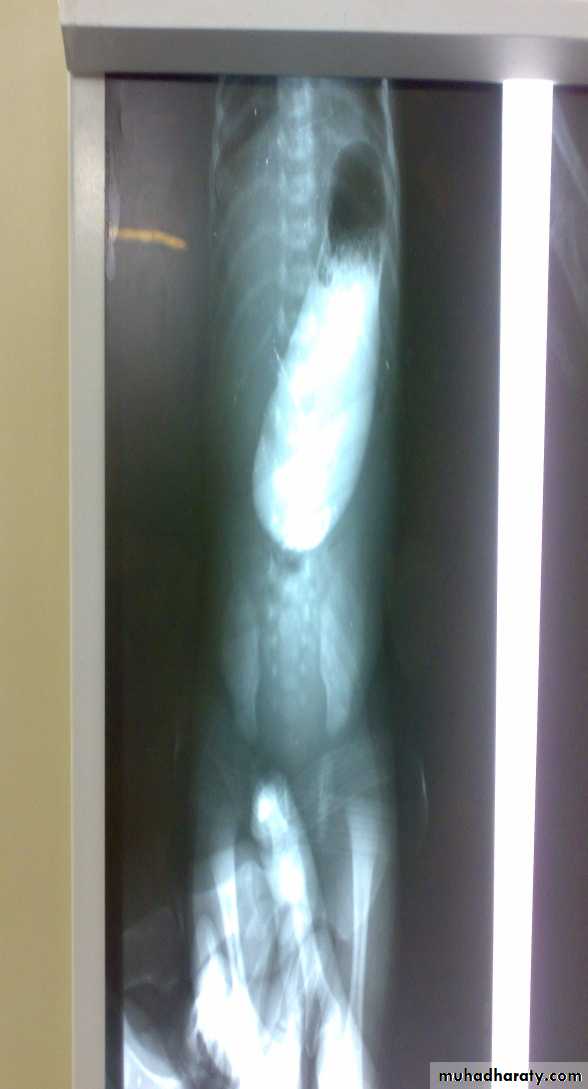

Bowel Obstruction

Hirschprungs disease